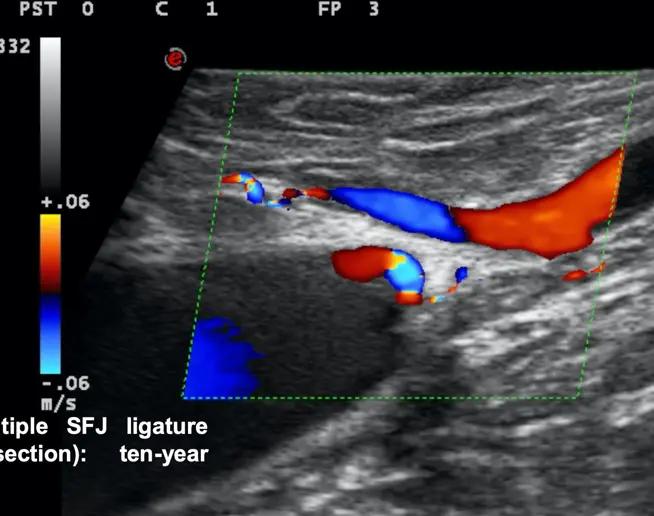

Procedure mini-invasive in anestesia locale, previo marcaggio  B-mode dei siti di interesse chirurgico definiti nella cartografia emodinamica.

Cartografia e strategia personalizzate in base al tipo di shunt in ogni singolo paziente.